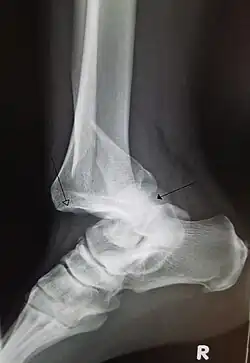

| Other names | Latin: luxatio |

| A traumatic dislocation of the tibiotarsal joint of the ankle with distal fibular fracture. Open arrow marks the tibia and the closed arrow marks the talus. | |